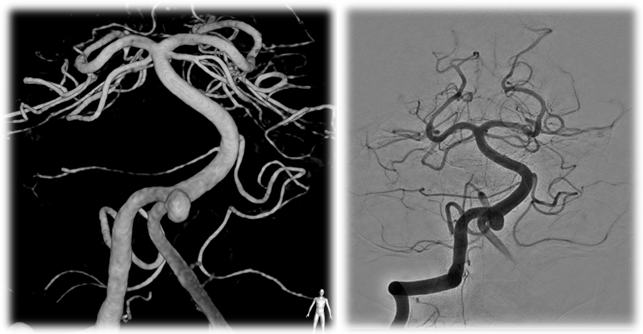

University of Massachusetts becomes the first hospital in the United States to use the Atlas Stent for Stent-Assisted Coiling of Cerebral Aneurysm

Date Posted: Saturday, August 01, 2015On June 30, 2015, Dr. Ajit S. Puri became the first physician in the United States to use the Atlas Stent for cerebral aneurysm stent-assisted coiling treatment for one of our neurointerventional patients. Endovascular treatment of cerebral aneurysms is a minimally invasive technique that has evolved rapidly since the first detachable coils were used to treat a patient in 1991. The procedure involves accessing the brain’s blood vessels with tiny plastic catheters introduced through a small puncture in the groin. The embolization coils used to treat the aneurysm are made of a metal that has a memory so that when the coils are advanced into the aneurysm, the metal unfolds, filling the space within the aneurysm. Advanced techniques in endovascular therapy have evolved to allow for the use of stents, similar in concept to the types of devices used to treat coronary artery disease, as an adjunctive therapy to treat wide-neck aneurysms. The stents serve as scaffolding for coil placement and prevent intrusion into the “parent” artery while allowing for the maximum number of coils to be deployed within the aneurysm.

Figure 1-Pretreatment images of the aneurysm |

Figure 3: Final angiographic result. Note the red arrows showing the final coil mass. |

Figure 2: Intraprocedural Images of First Atlas Case. Note the red arrows indicating the radiopaque markers on either end of the stent. |